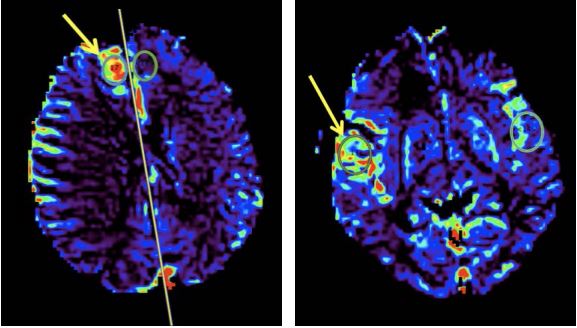

Перфузійно-зважені МРТ-зображення були оброблені за допомогою пакета Olea Sphere® (Olea Medical®) для відображення карт об'єму мозкової крові та K2 (проникність). Були визначені області інтересу і оцінені відповідні перфузійні карти.

Об’єм мозкової крові: Об’єм мозкової крові підвищений при парафакторіальному ураженні (зліва), тоді як при лобово-очноямковому ураженні він є нормальним (справа). Значне підвищення CBV в парафасціальному ураженні зумовлене пухлинною гіперваскуляризацією. Навпаки, у фронто-оперкулярному ураженні кровонаповнення еквівалентне нормальній паренхімі і дещо знижене в периферійних ділянках ураження (на карті позначено зеленим кольором).

Значення пухлини: 4.01Значення пухлини: 1.29

Нормальне/референтне значення: 1.25Нормальне/референтне значення: 1.47

Відношення: 3.21Відношення: 0.87

K2: Карти проникності показують підвищений рівень K2 в обох ділянках ураження. Обидва ураження мають підвищену капілярну проникність.

Значення пухлини: 182.48Значення пухлини: 122.98

Нормальне/референтне значення: 28.57Нормальне/референтне значення: 58.97

Відношення: 6.39Відношення: 2.09